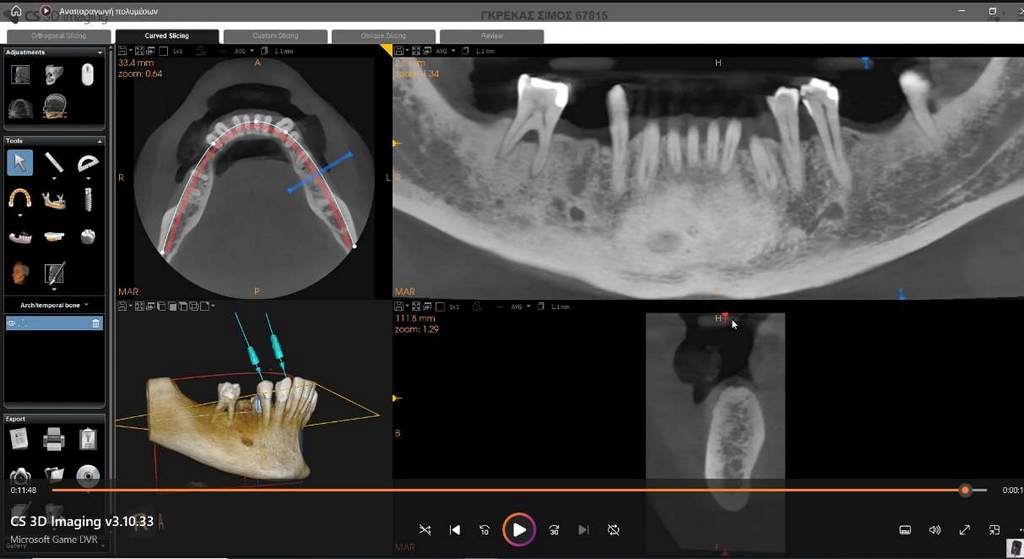

Σήμερα, στο «οπλοστάσιό» μας, έχει προστεθεί και η υπολογιστική τομογραφία κωνικής δέσμης (CBCT), οι εικόνες της οποίας είναι ιδανικές τόσο για να μας πληροφορήσουν για τη μορφολογία του συστήματος των ριζικών σωλήνων αλλά κυρίως να μας βοηθήσουν στη διάγνωση των βλαβών στο άκρο της ρίζας, στην έκταση αυτών των βλαβών και τη σχέση τους με παρακείμενες ανατομικές δομές (π.χ. ιγμόρειο).

Ατελής ενδοδοντική θεραπεία που οδήγησε σε περιακρορριζική καταστροφή.

Η επανάληψη της ενδοδοντικής θεραπείας δεν οδήγησε σε πλήρη επούλωση της βλάβης,

καθώς είναι αναγκαία και η περιοδοντική θεραπεία του δοντιού.

Χρόνια φλεγμονώδης περιακρορριζική βλάβη, κυρίως,

λόγω ενδοδοντικής αιτιολογίας. Μετά την ενδοδοντική θεραπεία

ακολούθησε περιοδοντική θεραπεία.

Δύο χρόνια μετά, παρατηρείται πλήρης εξαφάνιση της βλάβης.